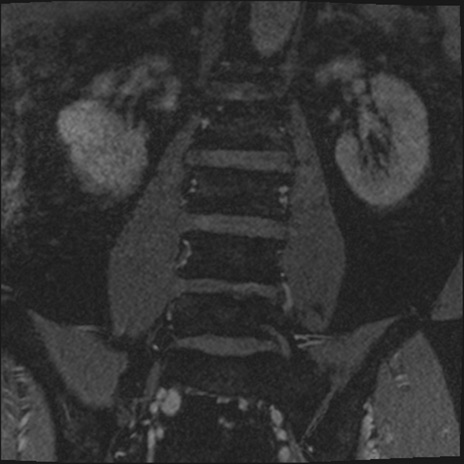

【整形】TIPS症例2 腰椎MRI 3D(冠状断像)

【症例】70歳代男性

【主訴】左下肢痛

【現病歴】2週間前くらいから腰痛、左下肢痛あり。左臀部から大腿、下腿外側のしびれが常時ある。歩行とともに同部位の痛みあり。

【身体所見】Lasegue70-/60+、Bragard-/±、PTR ±/±、ATR -/-、IP 5/5、TA 5/4、TS 5/5、EHL 右第1足趾なし/3、FHL 5/5、hypersthesia(-)、足背動脈触知良好

異常所見と診断は?